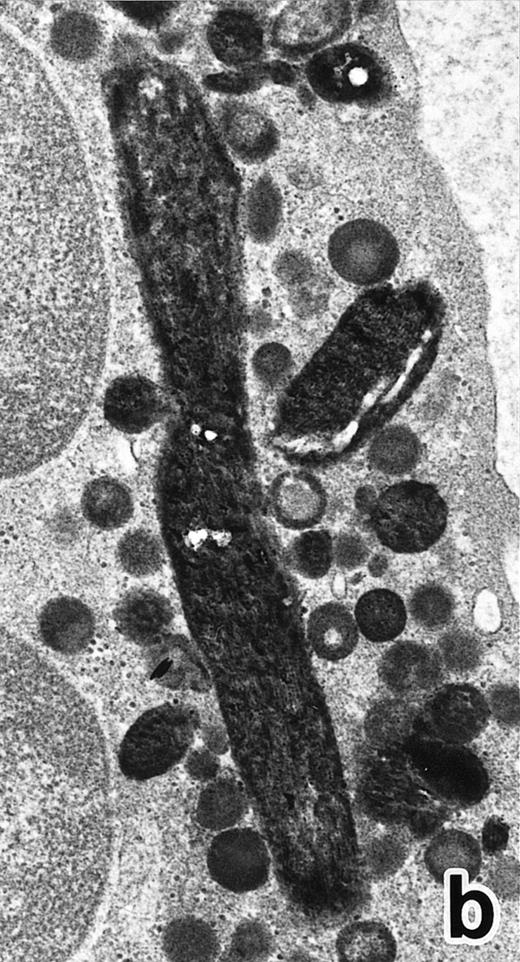

(a) A PMN in patient no. 1 that appeared after 4 weeks of ATRA treatment. (MPO-stained section, original magnification × 14,900.) (b) Higher magnification of a portion of the cytoplasm in (a). Note that, in contrast to the cells in Fig 5, this cell contains two types of cytoplasmic granules, ie, MPO-positive spherical granules and MPO-negative, elongated or dumbbell-shaped, small granules (arrow), corresponding to the primary and secondary granules of neutrophils, respectively. (MPO-stained section, original magnification × 30,000.)